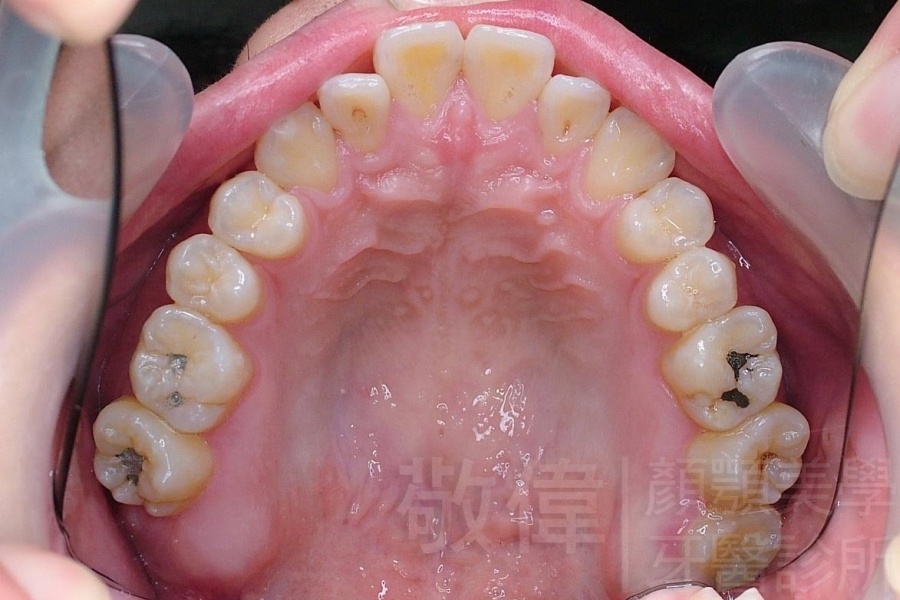

齒顏矯正/戽斗、亂牙、爛牙,變身 免植牙的健牙美女

<個案說明>

變臉矯正,原來戽斗妹跟大歪臉變成自信正妹

經由本院3D數影X光影像儀分析、與3D齒顎顏矯正技術,再配合口腔顎面正顎專科醫師施以正顎手術治療,雙方共同合作,使患者臉部外觀有很好的改善,大歪變小歪,產生了天南地北的大改變,她的人生也整個變得不一樣。